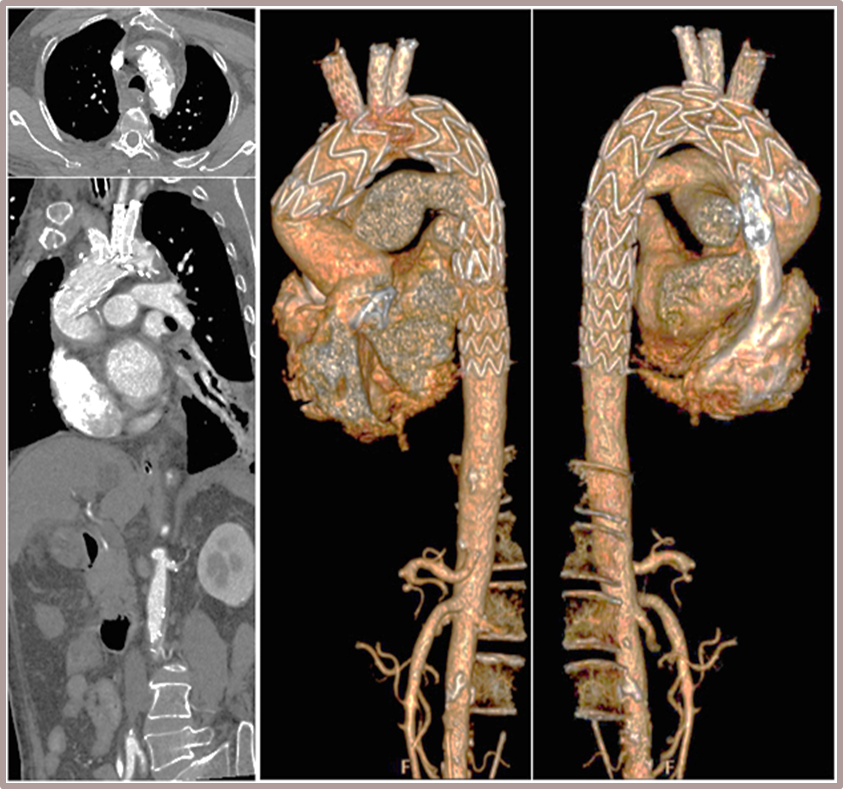

★ Case 4

男性,71岁,间断胸痛半年,加重7+天

高血压1+年,收缩压最高160+ mmHg

既往史和手术史:保守治疗1+月,弓部血肿增厚,胸痛加重

夹层动脉瘤CTA:主动脉夹层(非A非B型),累及主动脉弓至腹腔干发出平面以上腹主动脉,真腔小,假腔大;主动脉弓及左颈总动脉、左锁骨下动脉近端管径增粗,合并壁内血肿

术前影像

股-升主动脉支架

颈-无名动脉+左颈总动脉支架

股-弓部+左锁骨下动脉支架

术后复查